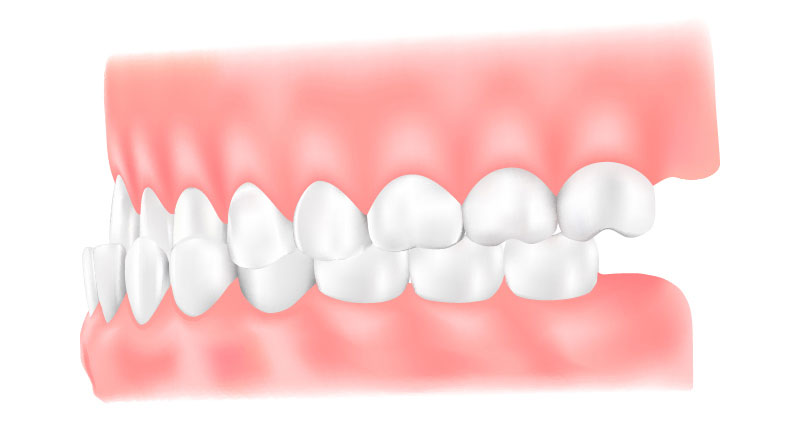

矯正歯科は、歯並びや噛み合わせを整える治療です。見た目の改善に加え、噛みやすさや磨きやすさが向上することで、むし歯や歯周病の予防にもつながります。また、噛み合わせが原因で歯周病が進行したり、歯が割れる、補綴物が壊れるといったトラブルが起きている場合には、その改善策として矯正治療を提案することもあります。

矯正歯科